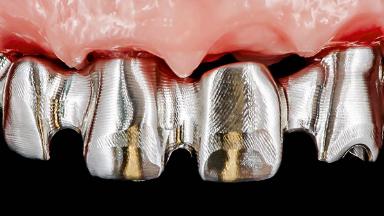

Rehabilitating an Edentulous Maxilla with a Fixed Dental Prosthesis Following Provisional Immediate Loading

This case features the flapless computer-guided placement of 7 bone-level implants, distributed to provide maximal support for the prosthetic framework. A rigid one-piece metallic framework was utilized as an interim restoration to reduce the risk of fracture associated with this prosthetic design. As part of the clinical examination, the SAC Assessment Tool was used, resulting in a surgical and restorative risk classification as “complex”.

SAC Level Complex

Defining Characteristics Fully edentulous upper jaw to be rehabilitated with an implant-borne fixed dental prosthesis

Loading Protocol Immediate